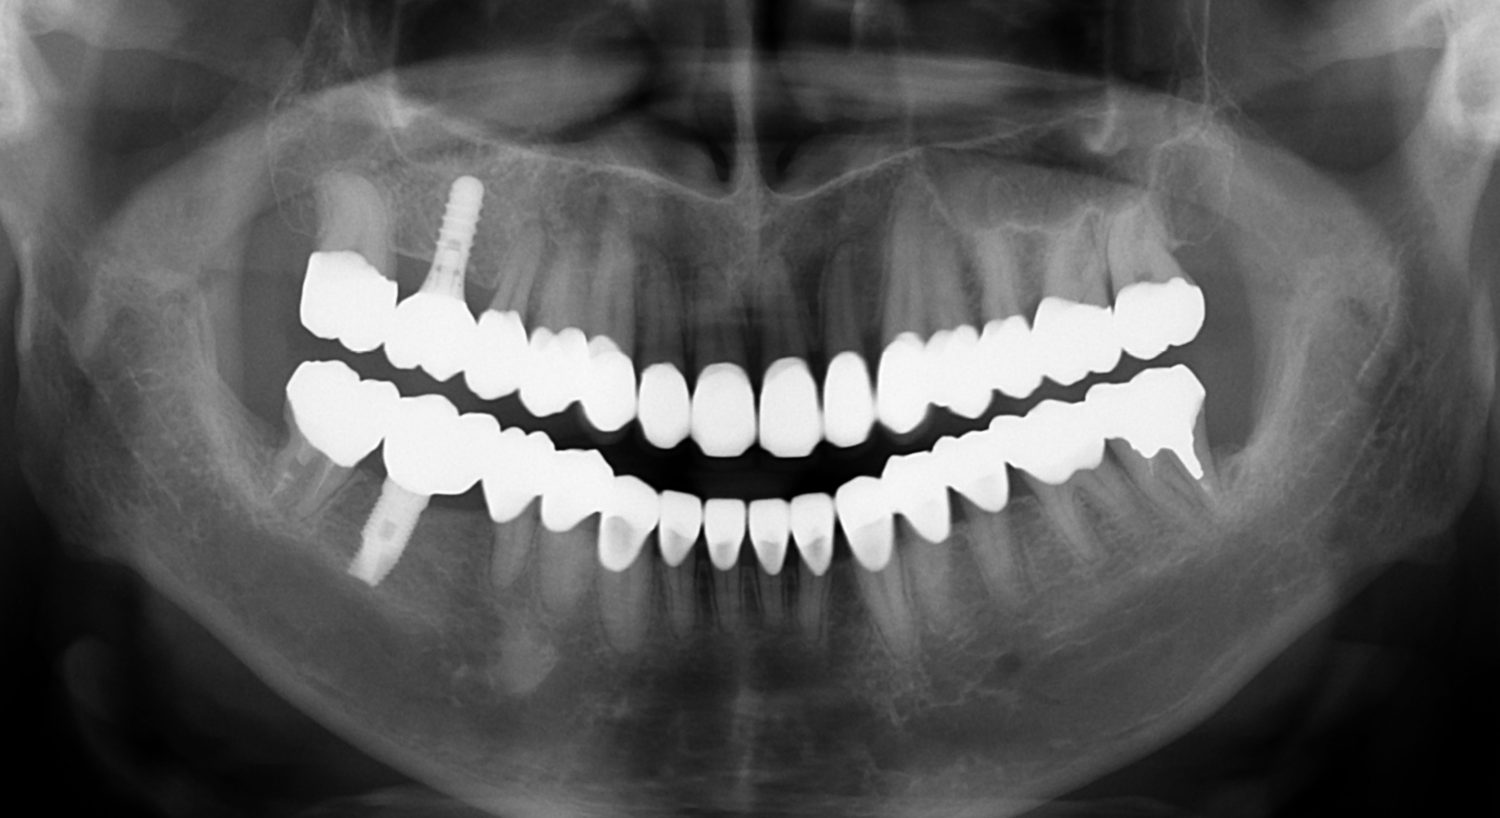

外科矯正治療・インプラント治療・セラミック治療の症例紹介(三隅歯科クリニック)

三隅 賢祐(三隅歯科クリニック)

症例詳細

| 主訴 | 50代男性 右上の歯と歯茎が痛い。どこで噛んでいいのか分からないので夜も眠れない |

| 治療内容 | 外科矯正治療・インプラント治療・セラミック治療を行いました。 |

| 治療費 | 4,500,000円(税込み) |

| 治療期間 | 4年(矯正治療期間 3年) |

| 治療回数 | 60回 |

| 想定されたリスク | 顎骨の変形があったので、全身麻酔下による外科処置が必要になり、身体的、精神的負担が増す可能性がありました。 清掃状況によっては矯正中にむし歯が発生するリスクがありました。 |